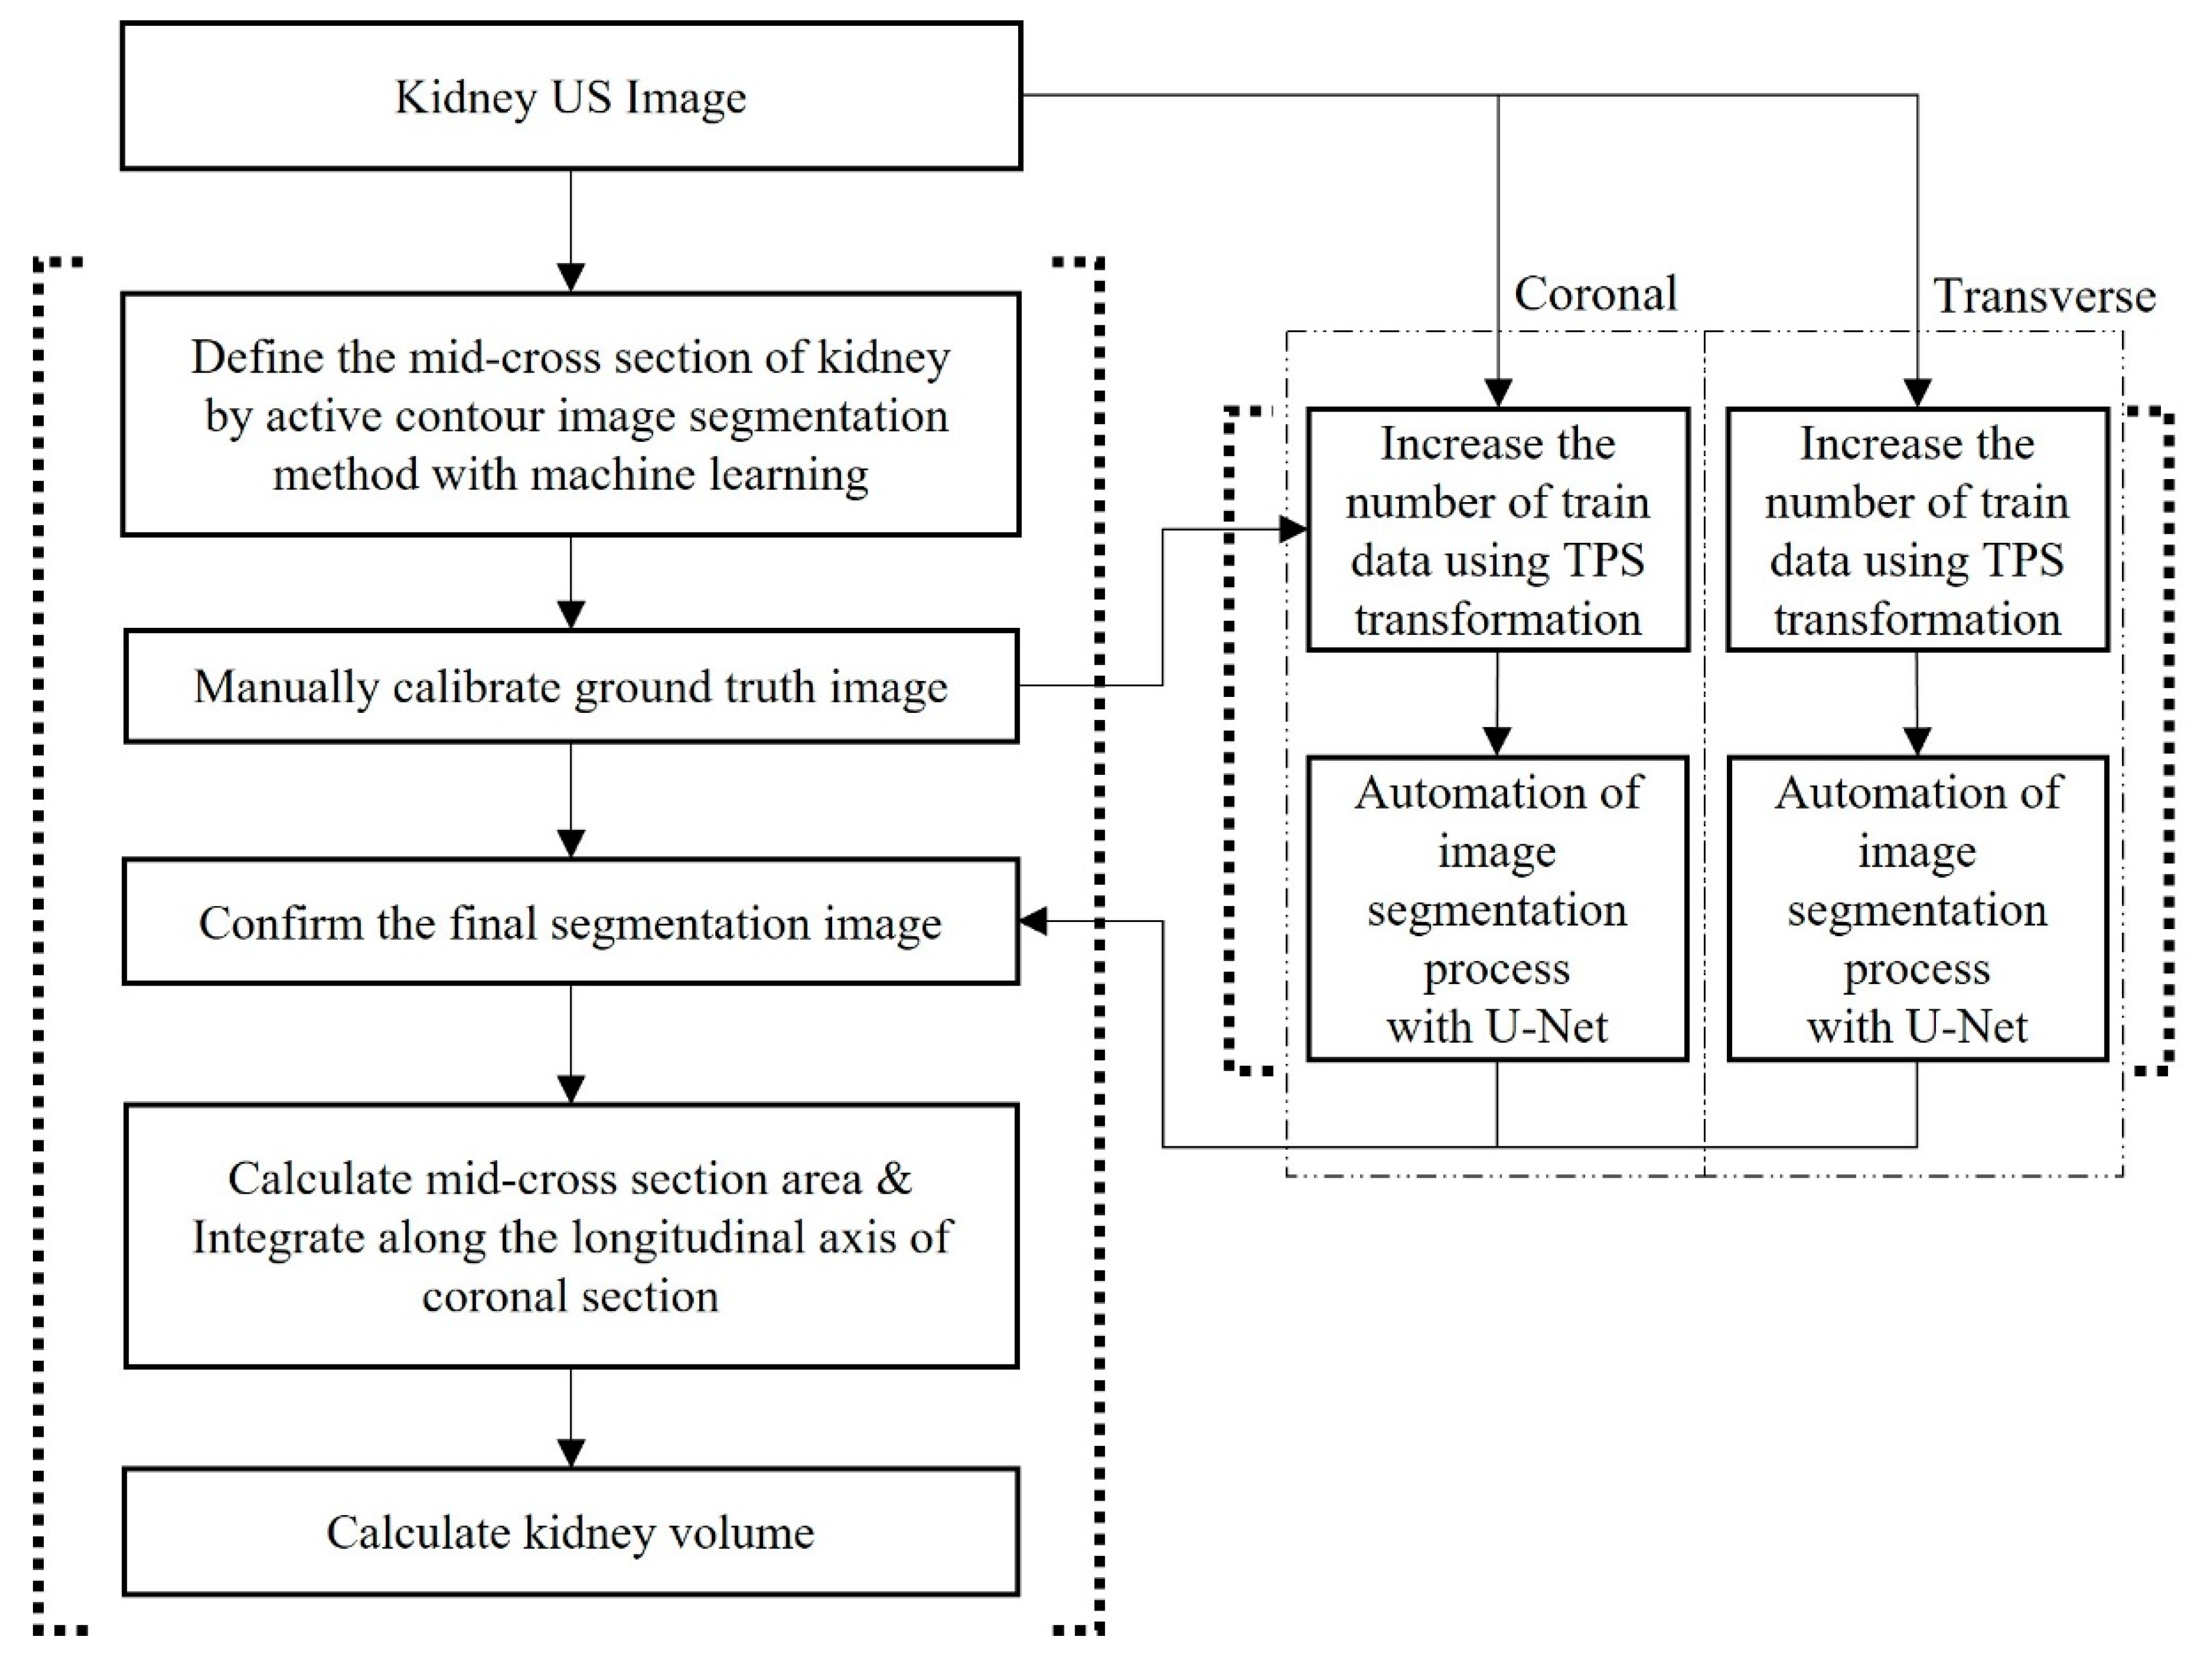

2.3.2. US Images and Image Processing Program

2.4. Automation of Volume Measurement by Hybrid Learning

2.4.1. Datasets

2.4.2. Data Augmentation Using Thin-Plate Spline Transformation

2.4.3. Deep Learning Network and Loss Function